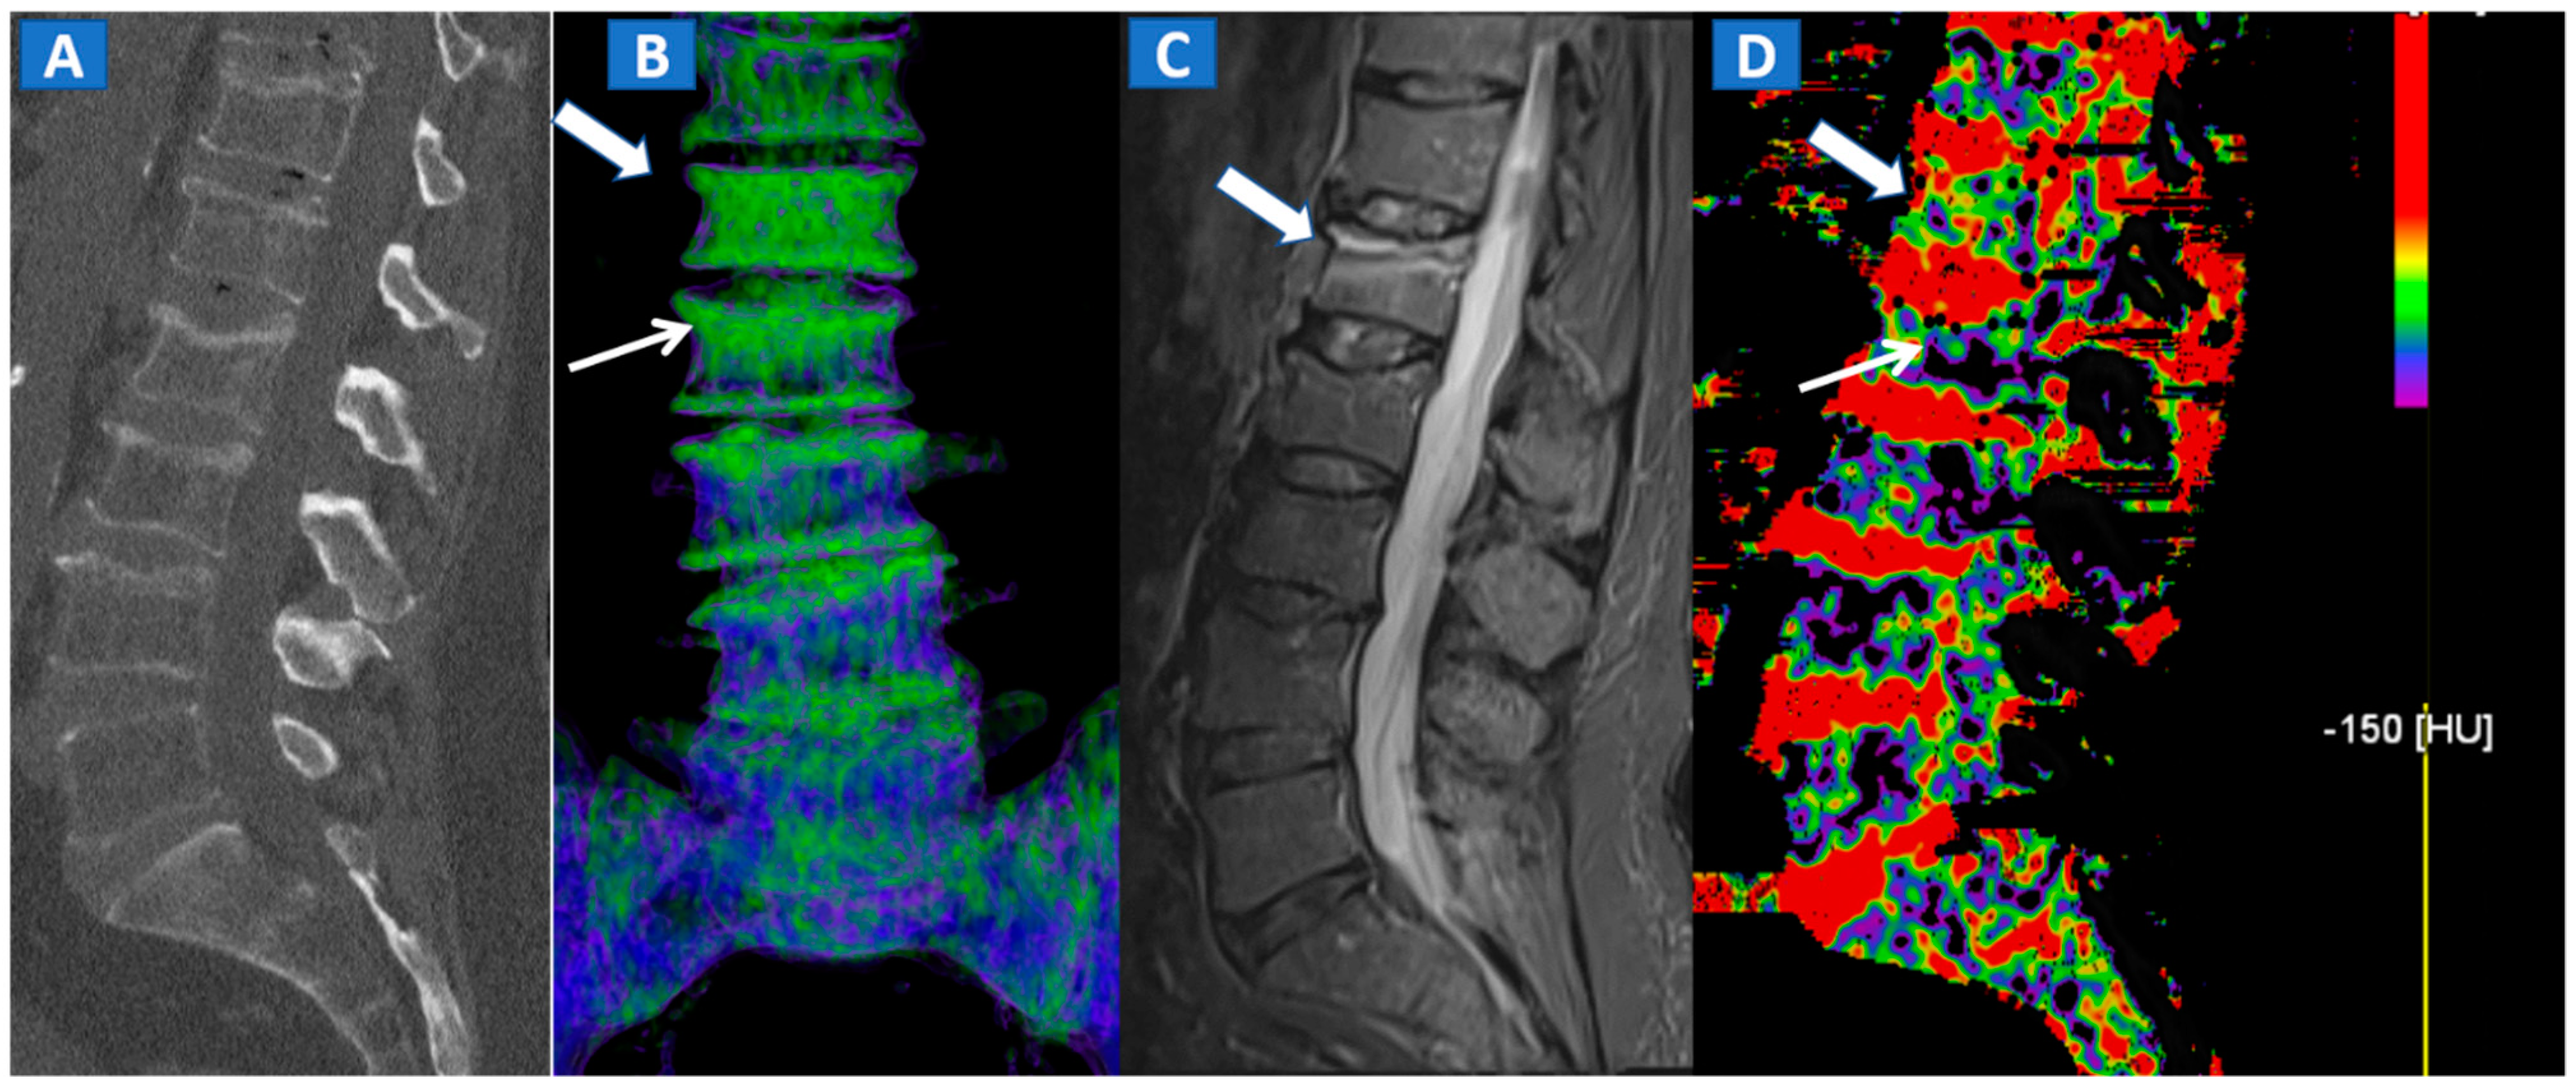

Figure 2.

A 62-year-old female with traumatic low back pain following a fall. On the sagittal standard 1 mm CT image (A) it is not possible to identify the fresh fracture. On the coronal 3D DECT image (B), BME of the L1 vertebral body is coded in green (thick arrow), with some mild oedema depicted on the L2 superior endplate (thin arrow). On the sagittal STIR MRI image (C), a fresh fracture of the L1 body is confirmed, with mild oedema located close to the superior endplate (thick arrow). There is no BME of the L2 body apparent on the STIR MRI image. On the corresponding 2D DECT image (D), the maximum level of superimposition of color-coded maps was used to confirm the presence of mild oedema on the L1 vertebral body (thick arrow) and to rule out the presence of significant oedema on the L2 body (thin arrow), thus avoiding a false positive finding.

4. The Spine

In cases of high-energy trauma, DECT images can help to rule out vertebral oedema, and reduce the reading time (Figure 1). When multiple vertebral fractures are present, DECT can identify fresh fractures that are typically characterized by the presence of BME (Figure 2). Furthermore, high resolution CT images can also be used to evaluate fine anatomical details such as transverse processes or posterior arches.

DECT 3D images are usually evaluated first, coding BME in shades of green and coding normal bone in blue (Figure 1). These images serve to provide a clear visual overview of the whole anatomical area, prior to any focus on specific findings. 3D images are usually more sensitive for depicting BME than 2D images (Figure 2). 2D images are analyzed by super-imposing the DE-specific information onto conventional grayscale morphological images (thickness, 1 mm; increment, 1 mm). Usually, a color lookup table is applied, which codes BME in shades ranging from green-yellow to orange-red (Figure 1C), with a range of densities set between −150 and 100 HU (Figure 1C). Superimposed color-coded maps are utilized only when density values are above the −50 HU cut-off. This approach can be useful in distinguishing between severe and mild BME (Figure 2). Additional windowing can also be carried out by increasing or decreasing the level of super-imposition of color-coded images in order to confirm or rule out subtler findings (Figure 2).